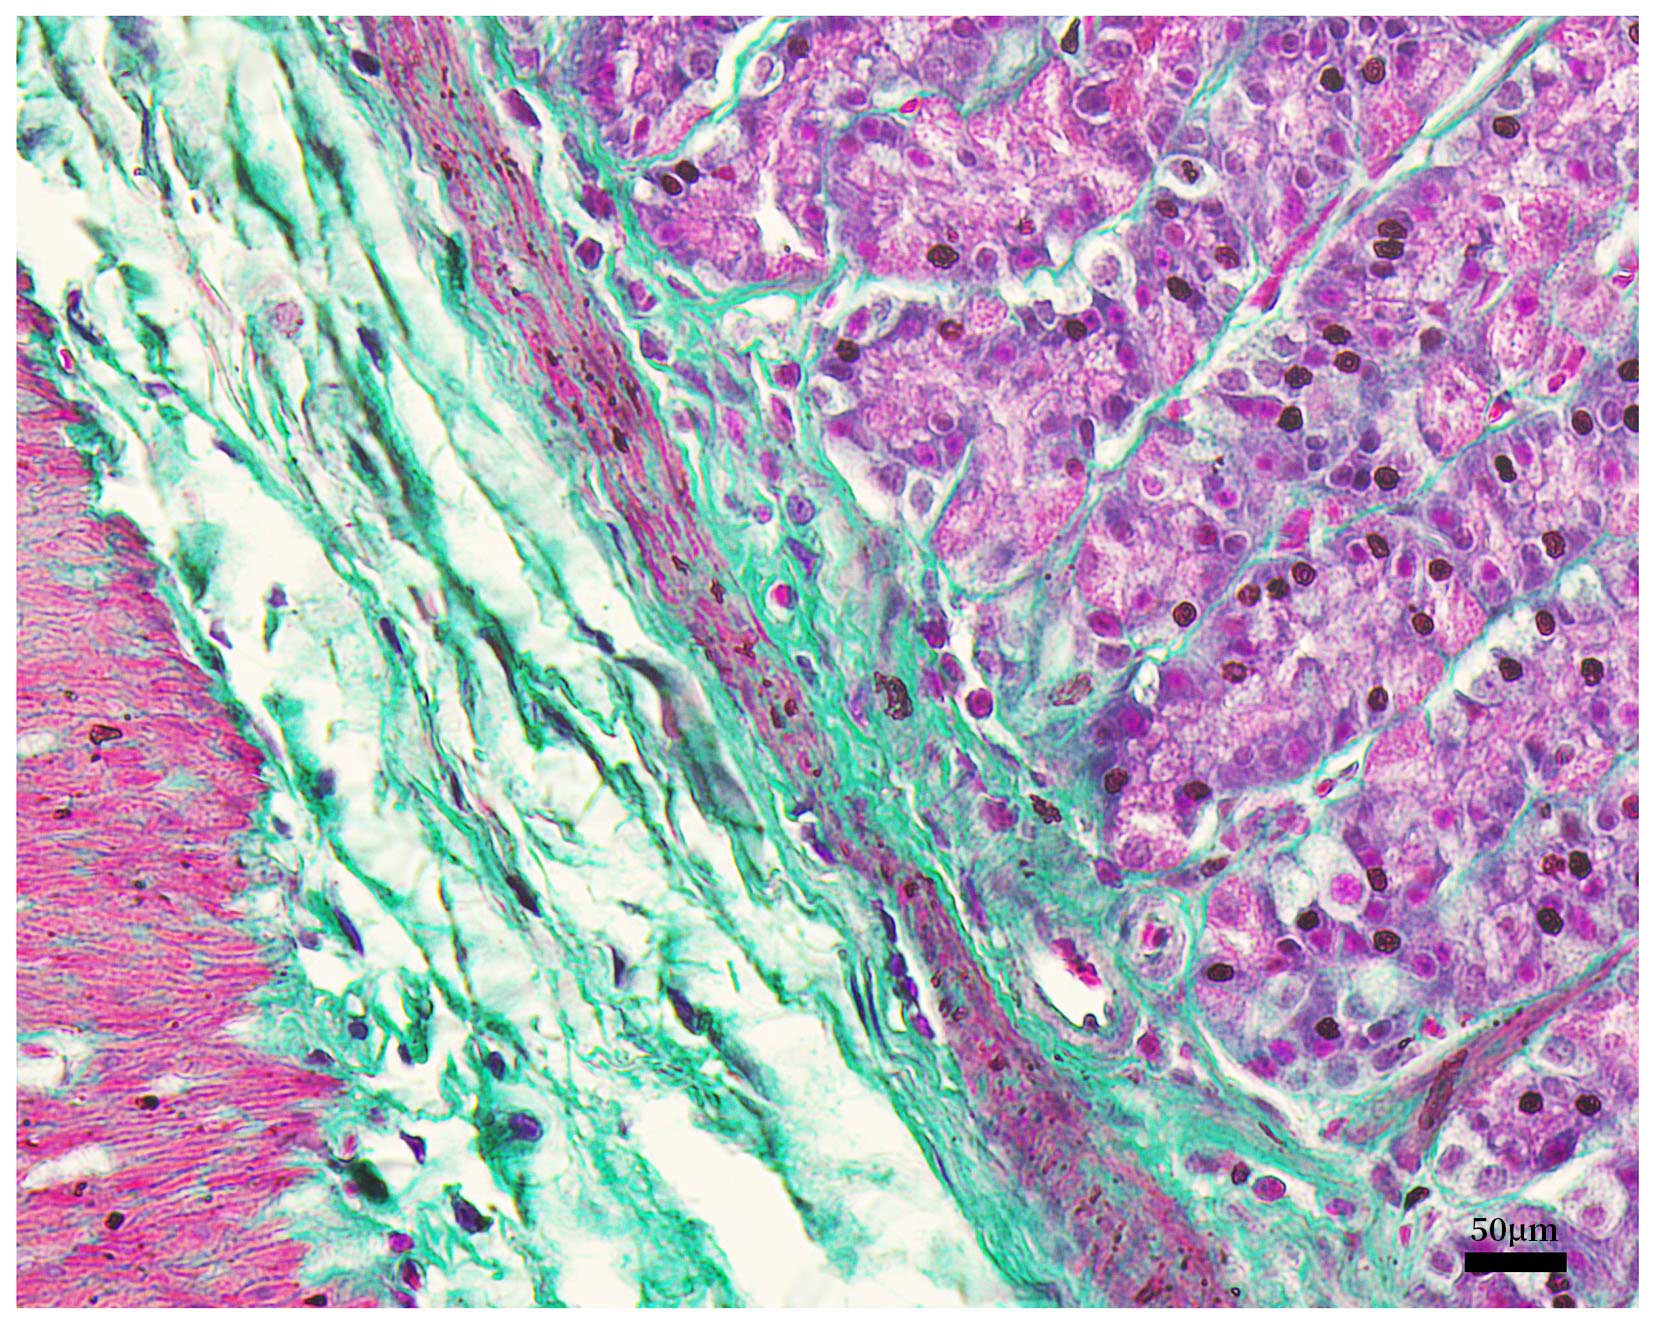

本试剂盒操作简捷,性能稳定,分化时间短,显色清晰,所染切片保存时间长且不易褪色,用于大鼠胃部石蜡切片的染色效果参考图1。

图1.碧云天Masson三色染色试剂盒(C0189)用于大鼠胃部石蜡切片的染色效果图。图中可见基底膜胶原纤维被亮绿染成绿色,胞浆被丽春红-酸性品红染成红色,细胞核被苏木素染成紫黑色。实际染色效果会因样品、检测条件的不同而略有差异,本图仅供参考。